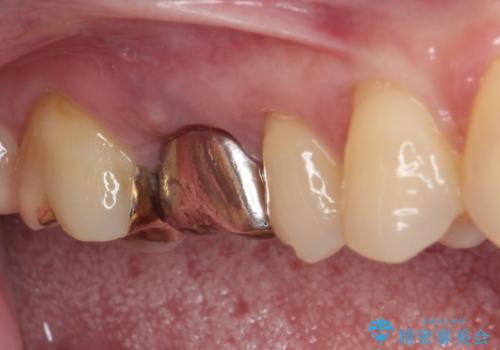

ゴールドインレーは銀歯のインレーやセラミックインレーと比べ、「技工操作の精度が高く、適合が著しく良い」というメリットがあります。特に上の奥歯は歯科医師の操作が行いにくいため、「適合の良さ」は再治療のリスクを防ぐ上でとても重要な要素となります。

上の奥歯は金属色が見えることもないため、審美的な問題は全くありません。

咬み心地はとても良好で、全く違和感がなく、患者様には大変満足していただきました。